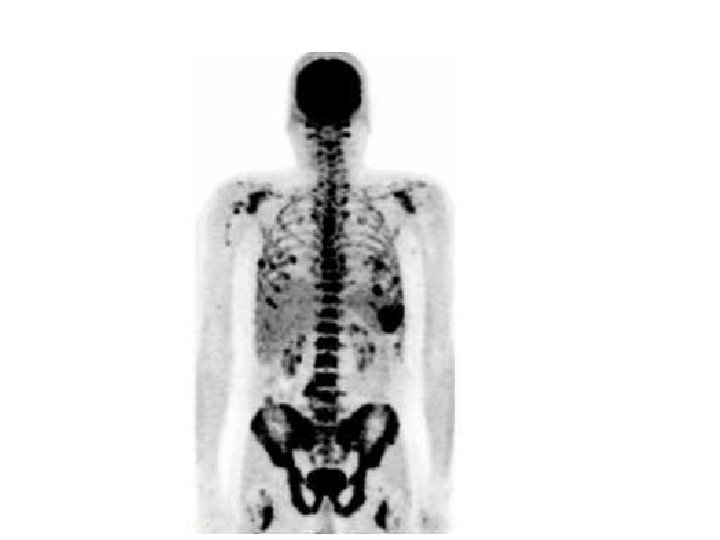

Myeloma • Multiple myeloma is a cancer in which abnormal cells collect in the bone marrow and form tumors. • Sometimes these abnormal cells (called myeloma cells) collect in only one bone and form a single tumor known as a plasmacytoma. • However, in most cases, the myeloma cells collect in many bones, forming several tumors and causing other problems. • When this happens, the disease is called multiple myeloma.

Bone Marrow Biopsy